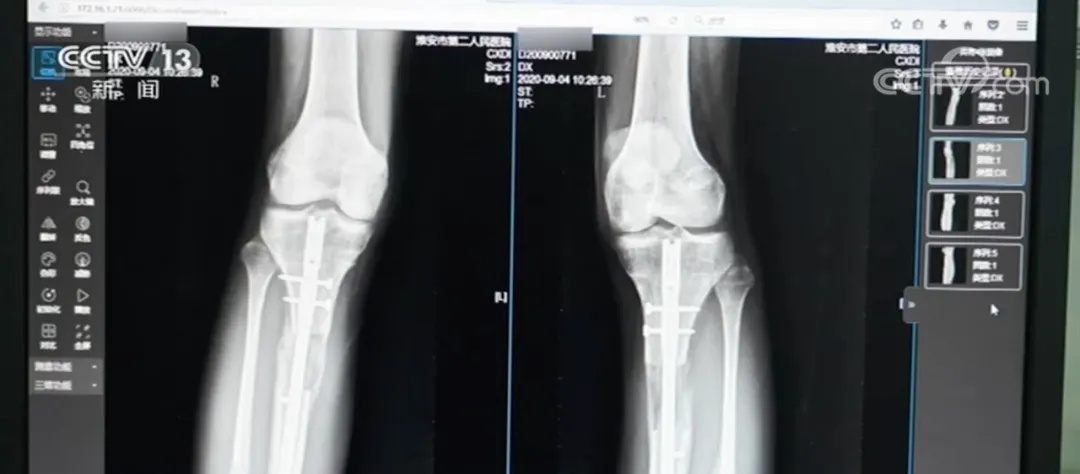

外架手术需要截断腿骨,用钢针穿透皮肤肌肉固定断骨,外部用圆环加固。术后每天需要调整支架旋钮拉伸双腿,全程需要一年半时间。内置手术则是沿腿骨植入电磁驱动髓内延长钉,通过体外遥控牵引,术后仅留2厘米微小疤痕且恢复期只有3个月时间。

然而,令小梦没想到的是,在术后第六个月,并发症突然来袭。小梦右小腿断骨处出现红肿溃烂,脓液不断渗出,被确诊为急性骨髓炎。此时,梁某还威胁她只有在群里说好话,才能接受后续安排的治疗。

如今,小梦体内的髓内钉至今仍未取出,因为取出手术可能引发二次骨折。更令她担忧的是,内置物中的磁铁成分可能会生锈,内固定装置还有断裂风险,小梦直言:“就像有颗定时炸弹藏在身体里。”

虽然小梦后续在国内接受了X型腿矫正手术,但效果并不理想。“我的腿脚经常酸疼,走路时间长了就会感到疲劳和僵硬,就像腿上绑着沙袋一样,断骨处也很疼,我不能像正常人一样起身、蹲下。”